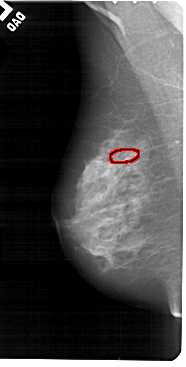

A_1553_1.LEFT_MLO

FILE: A_1553_1.LEFT_MLO.OVERLAY

TOTAL_ABNORMALITIES 1

ABNORMALITY 1

LESION_TYPE CALCIFICATION TYPE PUNCTATE DISTRIBUTION LINEAR

ASSESSMENT 4

SUBTLETY 1

PATHOLOGY BENIGN

TOTAL_OUTLINES 1

BOUNDARY